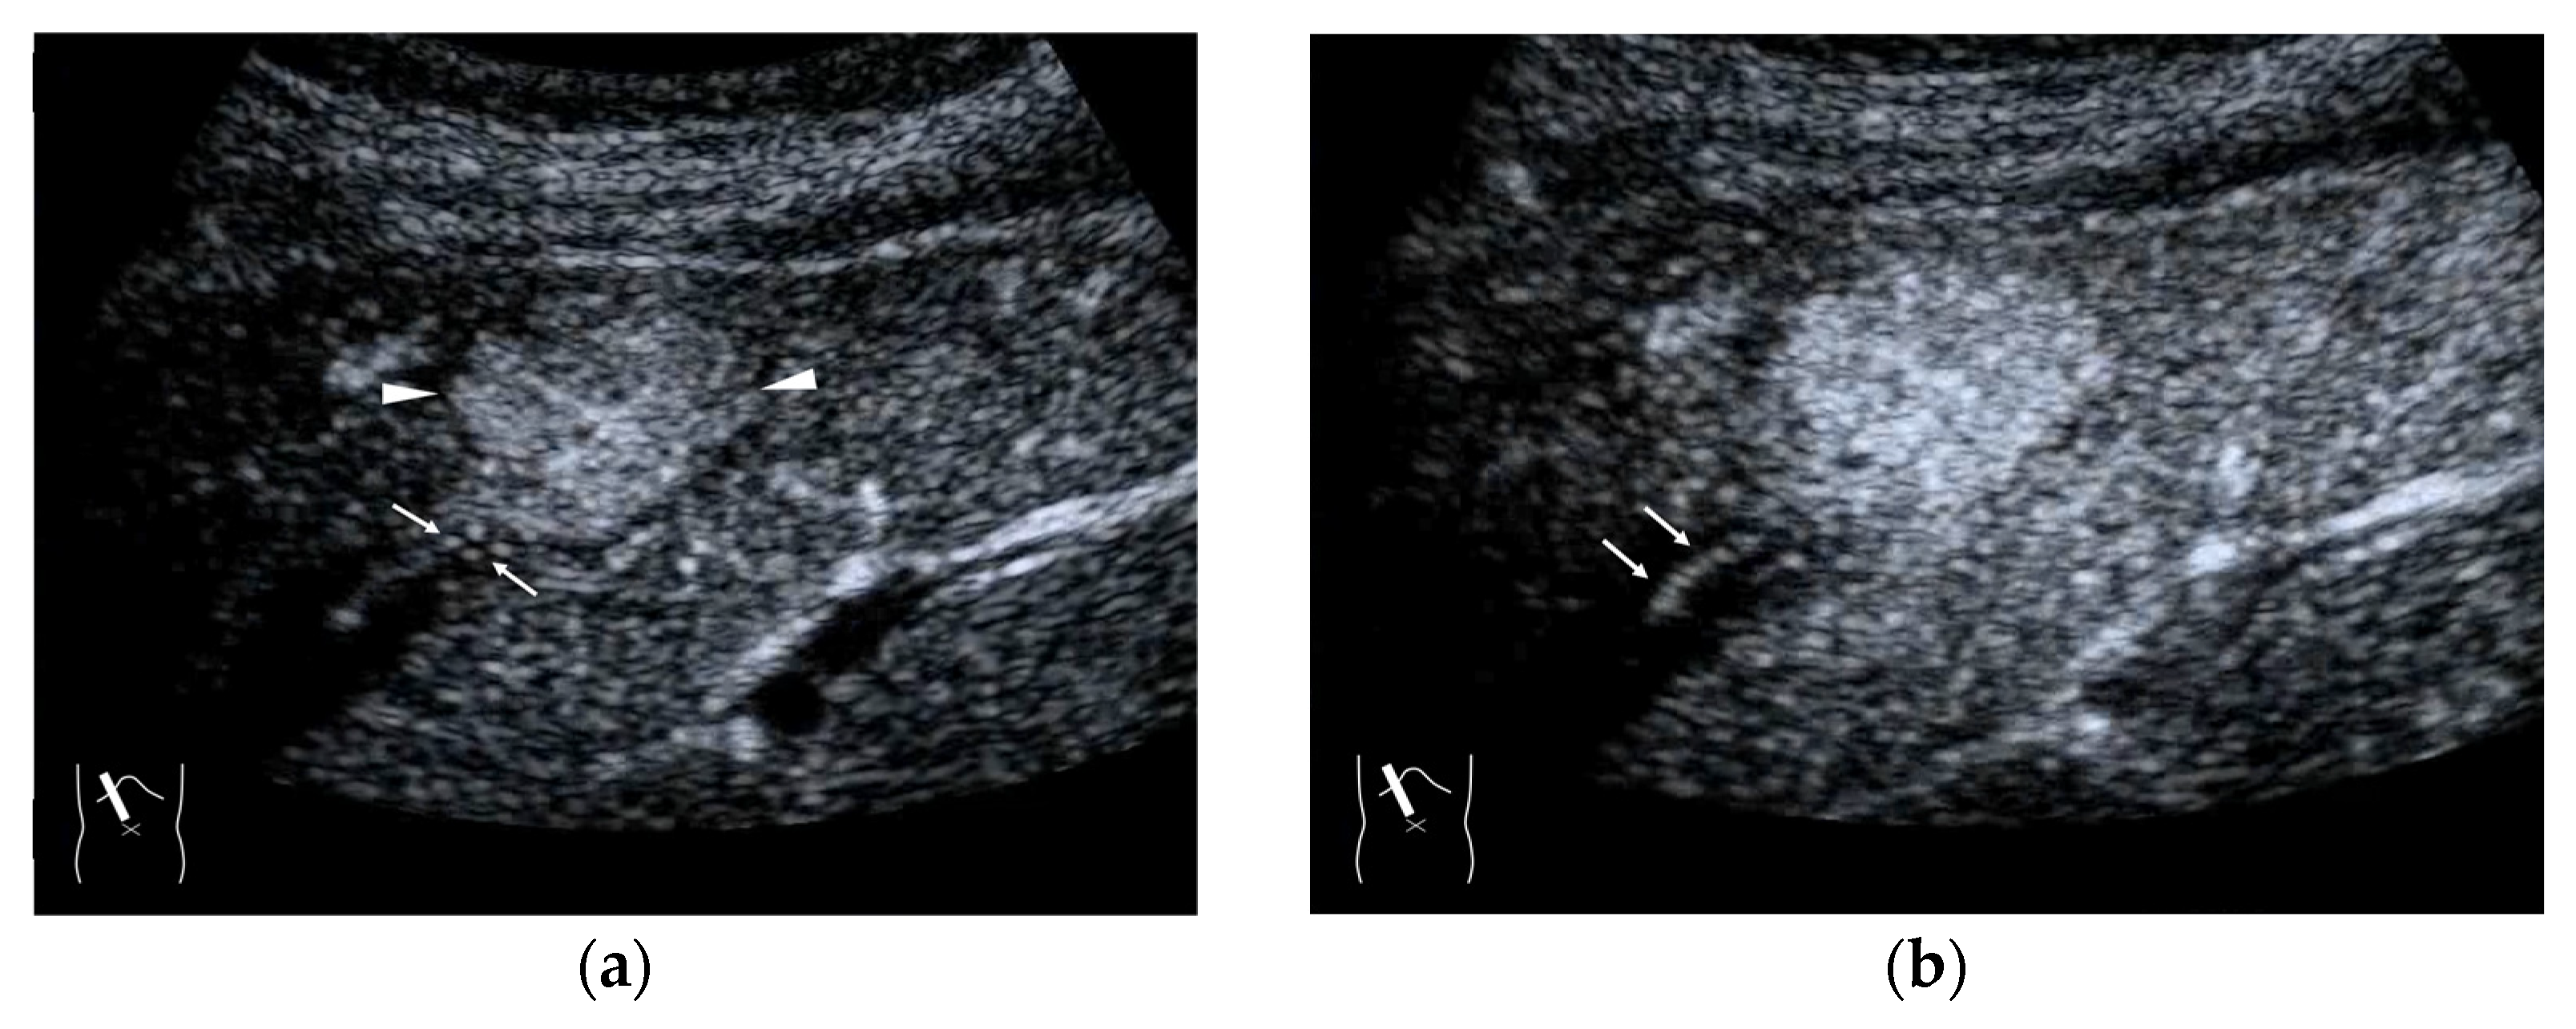

As mentioned above, the draining vessels of HCC also change significantly according to the histological changes in the background hepatic parenchyma. Thus, the CEUS findings must be comprehensively judged in combination with other clinical data. This complexity of the draining vessels also occurs in other malignancies, such as liver metastasis. Liver metastases [36] basically arise from an almost normal liver parenchyma without fibrosis: thus, there is no compression of the vasculature by fibrosis, as is seen in liver cirrhosis. The draining vessels of liver metastases are basically HVs, but due to the compression of the surrounding tissues by the tumor, numerous shunts are formed, some of the draining vessels may be portal veins, which complicates the process [37] (Figure 5a–c). According to some recent studies, hepatic metastases are divided into three types according to their growth patterns (desmoplastic, pushing and replacement patterns) [36,38]. The question of whether there is an association between the liver metastasis growth pattern and the draining vessel pattern is an important one that needs to be answered in the near future.

Figure 5.

Representative case of surgically resected solitary metastasis from small bowel sarcomatous adenocarcinoma: (a) The lesion (arrow heads) is well demarcated on B-mode US. (b,c) It is homogeneously hyper-enhanced (white arrows) in the arterial phase, and the tumor size appears to increase (yellow arrows), probably due to many surrounding fine vascular shunts.